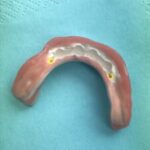

Auf Druckknöpfen gestützte Oberkiefer-Totalprothese, dadurch fester Sitz, kleinere Gaumenauflage